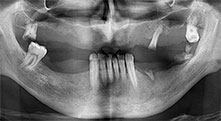

Un paciente de 40 años con una dentadura restante desastrosa desea someterse a un tratamiento mediante implantes. Como es fumador, en el maxilar superior no se planea una elevación del seno con prótesis dental fija, sino una prótesis mediante puente sobre cuatro implantes anteriores.

Implantes

Los cuatro implantes se encuentran in situ tal como estaba planeado. Los molares distales del maxilar superior sirven además para fijar la prótesis con base reconstruida, que se monta un mes después de la implantación.